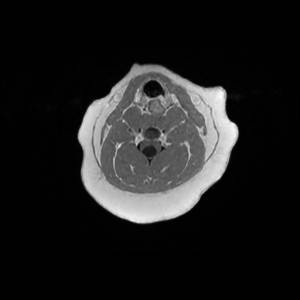

Main Gallery

Playing with a photo gallery function. It is possible to have multiple galleries, each within a namespace.